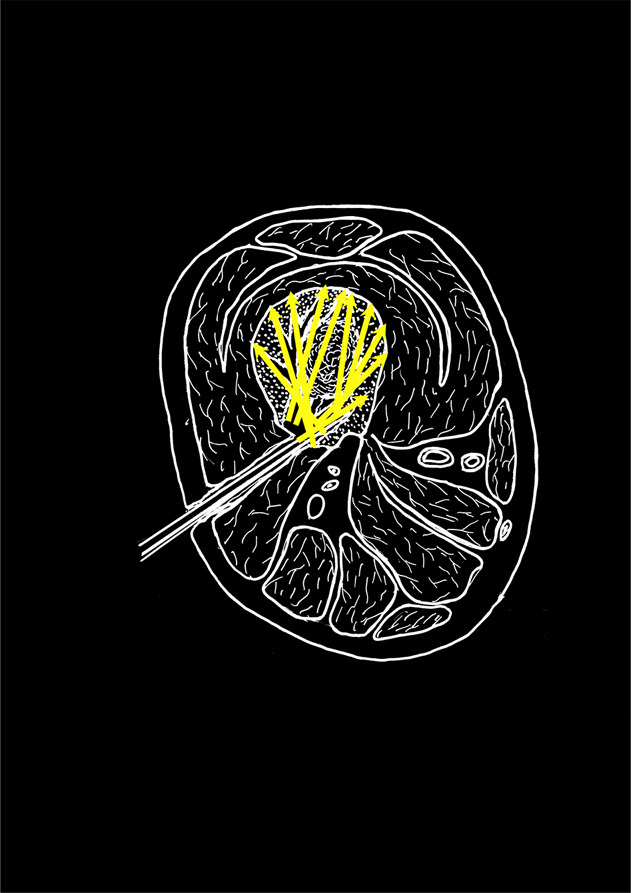

在世界各地,开放性骨折仍然是一个具有挑战性的临床问题,日本也不例外。外科医生在治疗这些损伤的整个过程中都面临着关键的决定,这些决定可能会对临床结果产生重大影响,包括抗生素用药的类型和时机、固定、软组织处理以及骨折后并发症的干预等。2022 年 10 月,日本骨折修复学会(JSFR)应邀作为主宾国学会代表日本参加了在佛罗里达州坦帕市举行的第 38 届创伤骨科学会年会。日本开放性骨折修复协会组织了一场题为 "开放性骨折及相关并发症的治疗--日本的方法 "的研讨会,会上介绍了日本治疗开放性骨折的前沿方法,包括 "固定-翻瓣 "法、局部抗生素灌注法和刺激骨愈合的 "削骨 "法。本文总结了研讨会上这 3 个演讲的内容。

Open fractures continue to be a challenging clinical problem throughout the world, and Japan is no exception. Surgeons are faced with critical decisions throughout the care of these injuries that can have significant effects in clinical outcome, ranging from the type and timing of antibiotic administration, fixation, soft-tissue management, and interventions for postfracture complications. In October 2022, the Japanese Society for Fracture Repair (JSFR) was invited to represent Japan as the Guest Nation society at the 38th Annual Meeting of the Orthopaedic Trauma Society held in Tampa, Florida. The JSFR organized a symposium, entitled "Management of Open Fracture and related complications-the Japanese way," that featured cutting-edge approaches to open fractures in their country, including presentations on the "fix-and-flap" approach, local antibiotics perfusion delivery, and a "chipping" method for the stimulation of bone healing. This article summarizes the content of these 3 presentations from that symposium.